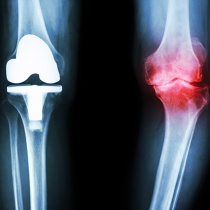

S’il a installé une prothèse, il contrôle à l’aide de la radiographie la bonne position et le bon fonctionnement de la prothèse.